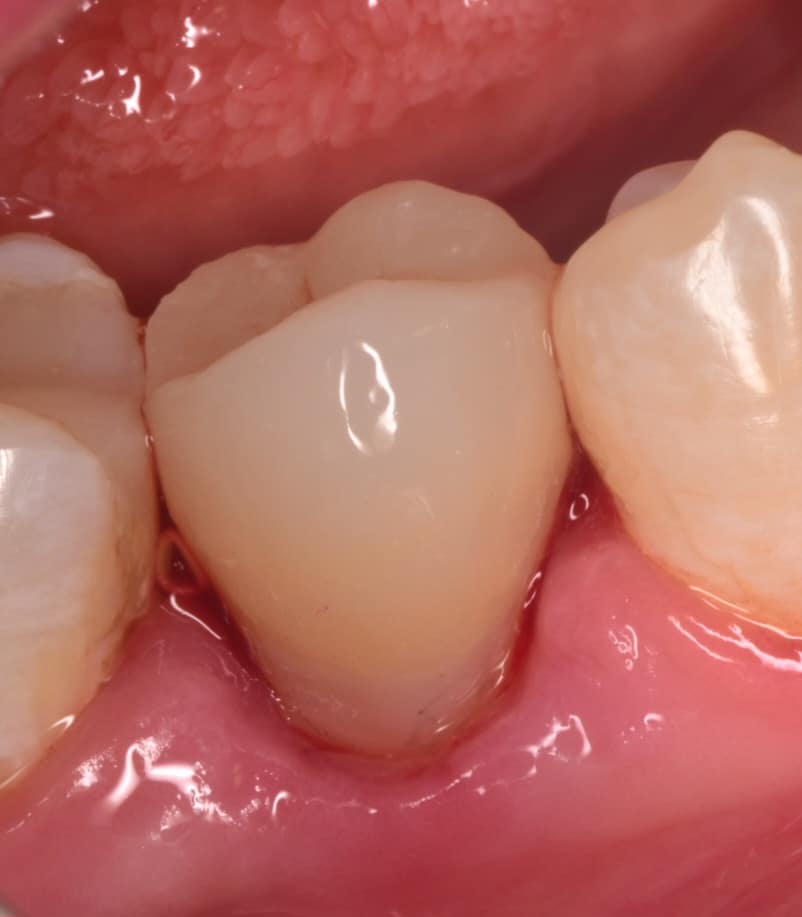

Initial situation showing badly carious lower second premolar

Buccal view showing the same destruction of the tooth, the patient insisted on restoring her tooth